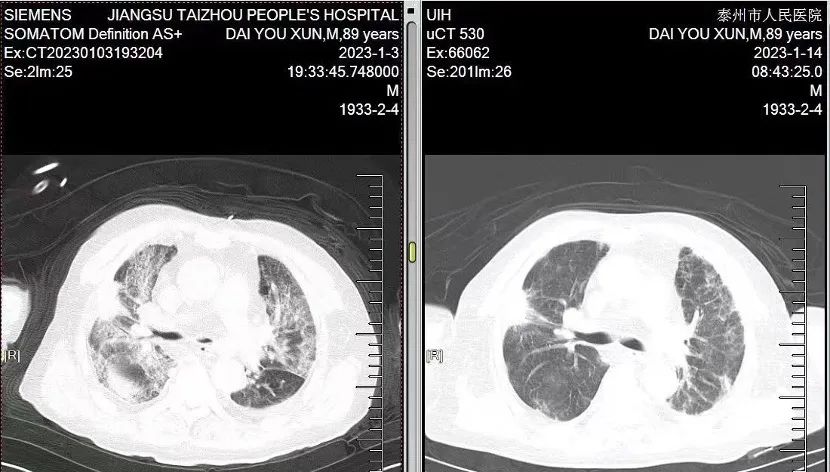

1月12日,今年90岁的戴爹爹血氧饱和度达到了正常水平,可他在1月3日晚上急诊入院时,却是一例“白肺”新冠重型患者,胸闷气喘症状明显,伴发热,Ⅰ型呼吸衰竭,低蛋白血症,加上长期高血压,病情陷入危险的境地,吸氧时血氧饱和度才80%。

“通过高流量吸氧和无创机械通气交替氧疗、俯卧位治疗及药物治疗等,患者的生命体征逐步改善,复查CT时显示大部分‘白肺’已经逆转,病灶吸收了很多,准备出院,给了我们很大信心。”

入院时 出院前

看到医生过来查房,老人家开心地打招呼、感谢。满面笑容、精神抖擞,丝毫看不出他刚刚经历了重症肺炎,甚至一度难以脱离氧气面罩。